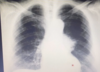

RN a termo.

Cardiomegalia massiva em um neonato com pulmão normal (sem edema alveolar ou intersticial, sem derrame pleural)

Cardiomiopatia neonatal.